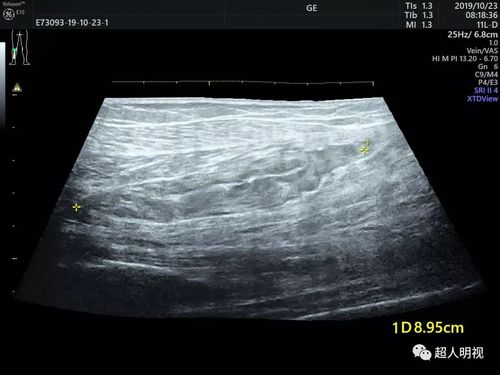

腓静脉超声位置示意图

腓静脉超声位置示意图,腓静脉位置示意图

小腿静脉解剖的超声图文分步解读

腓静脉超声图像